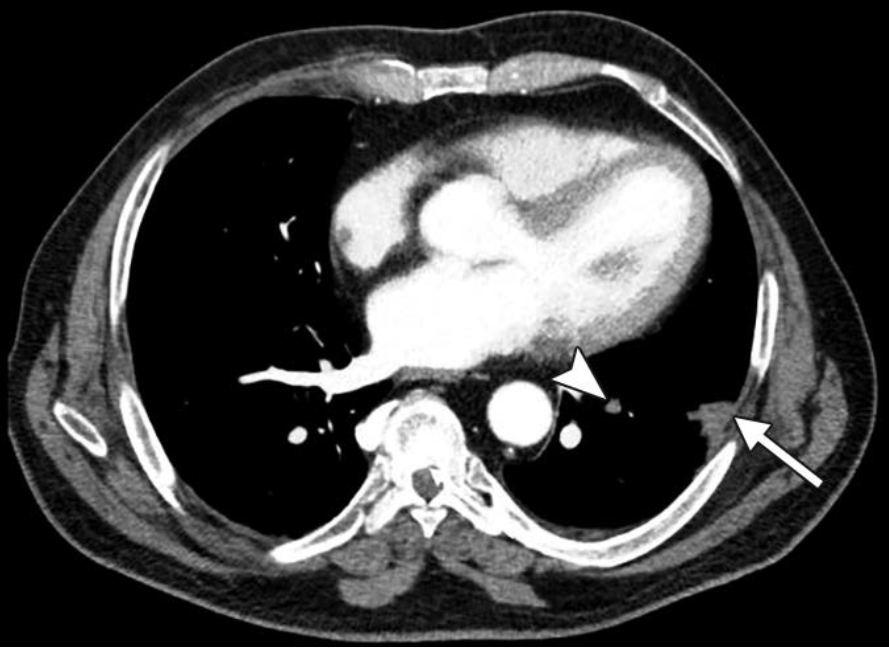

Standard Blended—We see the “What.” A classic peripheral wedge-shaped opacity: Hampton Hump (solid arrow). There is a subtle luminal filling defect in the feeding vessel (arrowhead), but in a motion-degraded scan, you might doubt it.